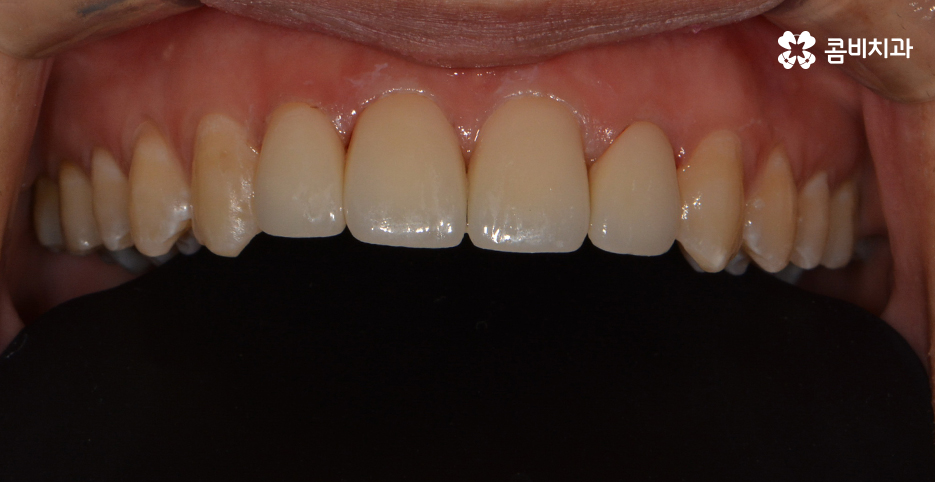

치열이 가지런하게 정렬이 된 상태에서 앞니 깨짐,

왜소치에 대해서 올세라믹이 진행되었습니다.

올세라믹은 세라믹 보철물로 치아 전체를 덮어 씌우는 방식으로

치아의 색과 모양은 물론 자연스러움을 위한 투명성까지도

갖추고 있으며 내구성도 높은 편이기 때문에 앞니가 깨졌거나

심한 변색, 충치, 왜소치 등의 치료에 많이 쓰입니다.